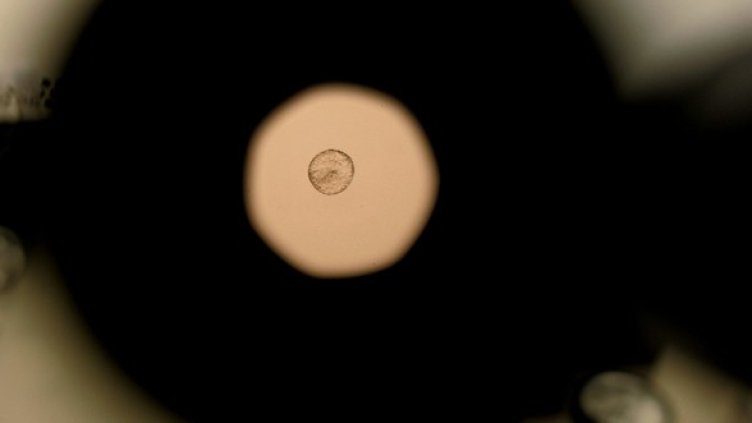

Смехът увеличава шансовете за успешно протичане на процедурата при изкуствено оплождане ин витро, съобщи Daily Mail.

Изследването, проведено от израелския професор Фридлър, показало, че само 15 минути смях на ден увеличават два пъти шанса за зачеване.

Резултатите са получени след направени анализи на над 200 жени, които преминали лечение от безплодие.

В началото на експеримента всички участнички били поставени в равни условия. Когато вече ембрионите били имплантирани, половината от доброволките били изпратени на представление с клоуни. То продължило 15 мин.

От групата на пациентките, посетили шоуто, процентът на забременелите бил 36,4 а в другата група – едва 20,2%.

Според професора тайната се крие в отпускането и понижаването на нивото на стреса.